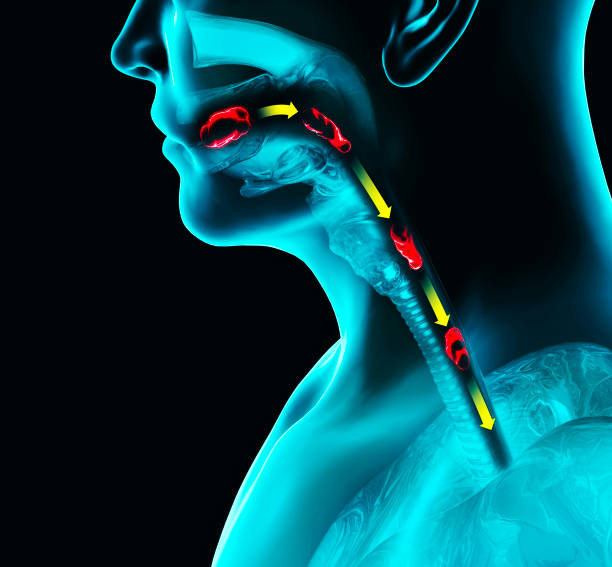

인후통

식도암이 위치한 상부 소화기관에는 식도와 인두가 있습니다. 이 중 식도가 암으로 인해 좁아지면, 음식이나 액체가 지나갈 때 통증을 느낄 수 있습니다. 이런 통증이 인후통으로 나타날 수 있으며, 식도암의 초기증상 중 하나입니다.